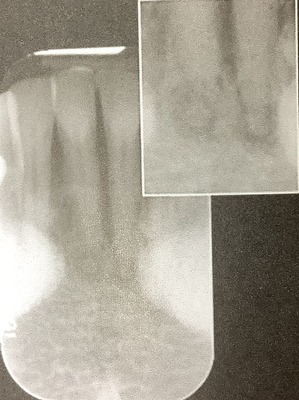

レントゲンで下の前歯の根っこに影が偶然に見つかった。

慢性根尖性歯周炎を疑われた。

でも根管治療をされた歯ではないし?

何も詰めたり、虫歯も無いのに、根っ子に影が有ります。